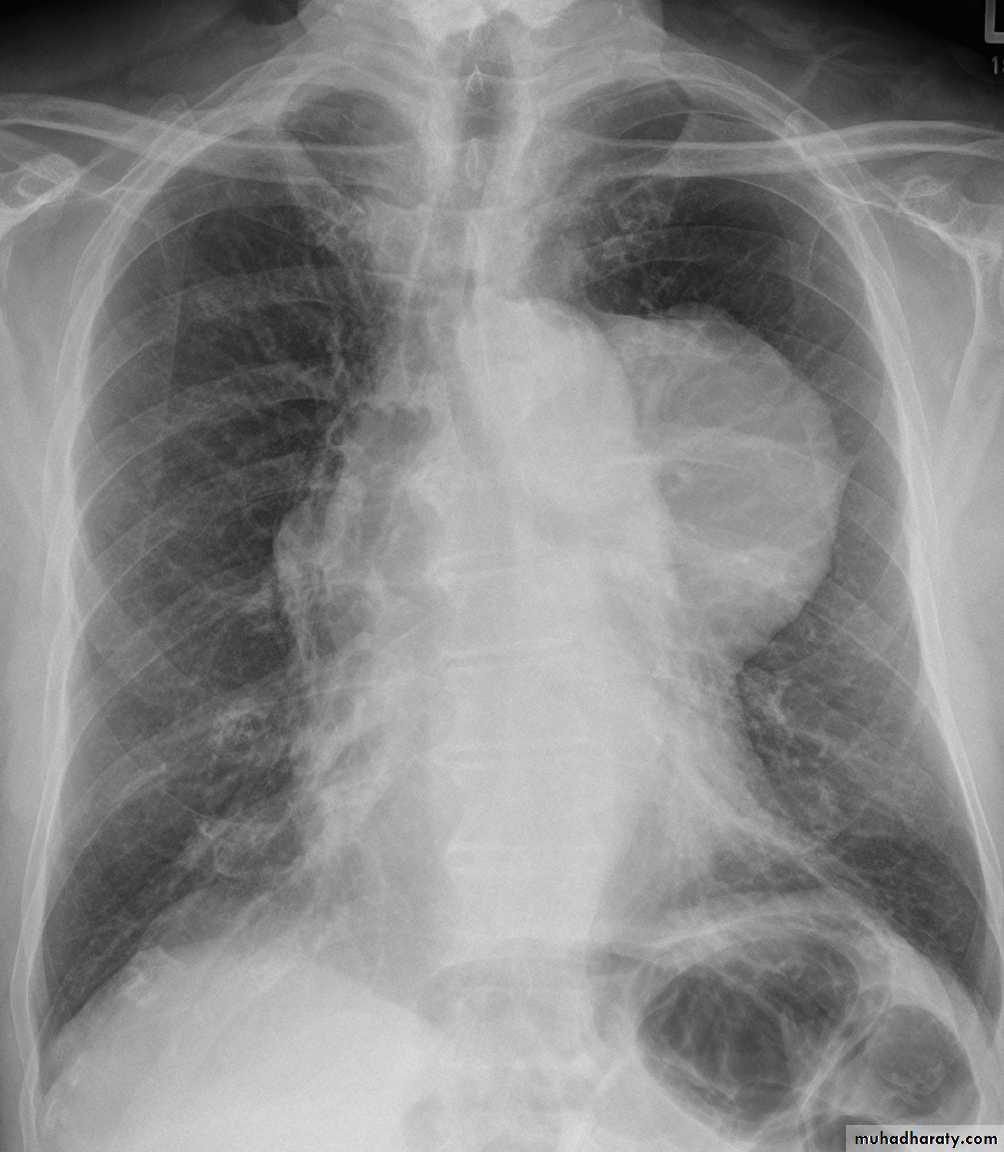

Hodgkin lymphoma of te middle mediastinum

Lymph adenopathy

Lymphoma is a malignancy arising from lymphocytes or lymphoblasts. Lymphoma can be restricted to the lymphatic system or can arise as extra nodal disease. This, along with variable aggressiveness results in a diverse imaging appearance.

Nodal disease

Hodgkin's disease is usually almost entirely confined to the lymph nodes.